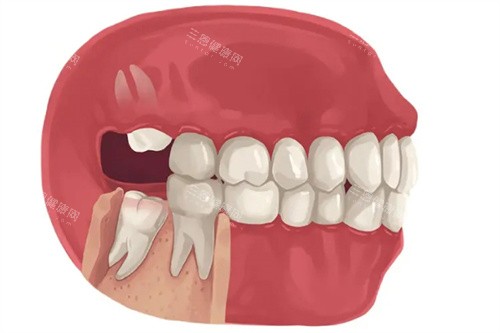

阻生智齿的不同类型

6. 急性炎症期的智齿

“疼得睡不着就去小诊所拔牙,结果脸肿成猪头!”网友@牙疼星人的教训很典型——智齿发炎(冠周炎)时,牙龈红肿、有脓液,此时拔牙易让感染扩散,医生会先降低炎症,等“平静”了再处理。